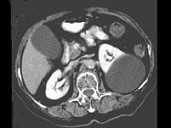

- 多项选择题女,38岁, 左腰部胀痛不适,CT平扫+增强如图所示, 下列说法正确的是 ( )

A、平扫时可见左肾一类圆形囊性病灶

B、病灶边界清晰,表面光整

C、增强扫描皮质期和实质期该病灶均未见强化

D、考虑为左肾囊性肾癌

E、考虑为左肾囊肿